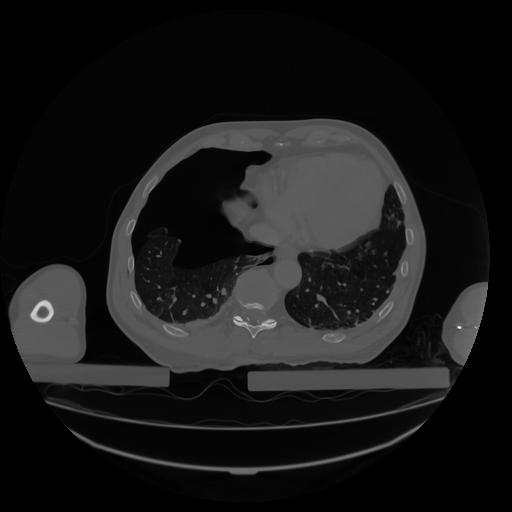

34 CUERPO,CE,Vol,1.0,CUERPO,,